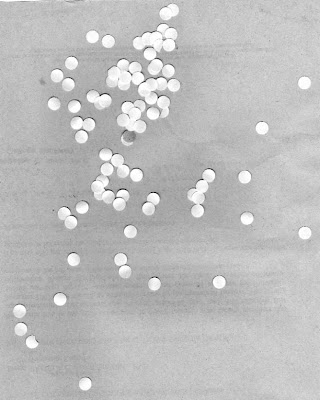

We can use the opening and closing operations to look for cancer cells (larger cells) in a pool of normal cells. Let's pretend that this image is an image of normal cells

|

| normal cells |

The goal is to separate the cancer cells from the normal cells. First we have to differentiate the normal cells from the cancer cells. We can do this by first determining the area of normal cells.

First, I cut the image into 256x256 subimages and binarized the images. Choosing carefully the threshold to separate the background from the cells. By looking at the histogram of the grayed image, we were able to determine the threshold (~0.84).

Binarized subimages.

The opening operator is then applied to separate closely placed cells. The strel used is a 5x5-pixel circle with the center at the topmost left 1-valued pixel.

Opened subimages.